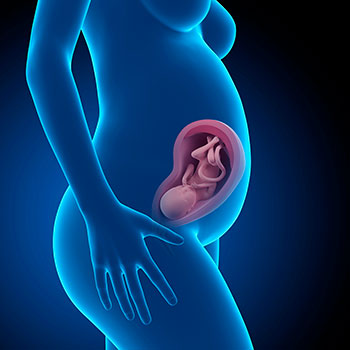

Na 30ª semana de gravidez, o bebé mede cerca de 39 centímetros e tem mais de 1 kilo de peso.

Os seus traços estão bem definidos e as suas proporções estão mais equilibradas. A cabeça já não é tão grande em relação ao corpo.

Se o teu bebé é um menino, neste período os seus testículos vão descer. O bebé continua a aumentar o seu peso, em parte porque a sua pele agrega novas camadas de vérnix caseoso, a gordura que o vai ajudar a regular a temperatura corporal e o vai manter protegido depois de nascer.

A sua pele já não está tão enrugada e agora está muito mais esticada. Já se começa a colocar na posição definitiva para nascer.

Idade do feto: 28 semanas.

Já bem consolidado no terceiro trimestre, o bebé cada vez tem menos espaço para se mexer. Apetece-te ver como está dentro do útero? Em seguida oferecemos-te a imagem de uma ecografia e de um vídeo que te vão surpreender. Espanta-te!